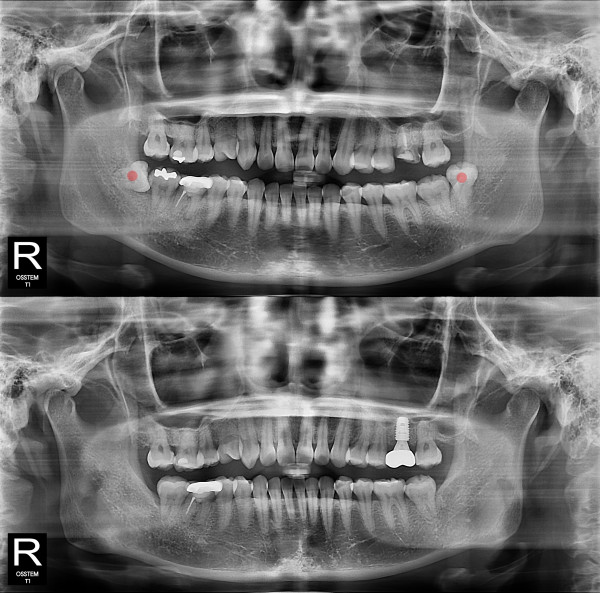

智齿拔除 部分埋伏智齿